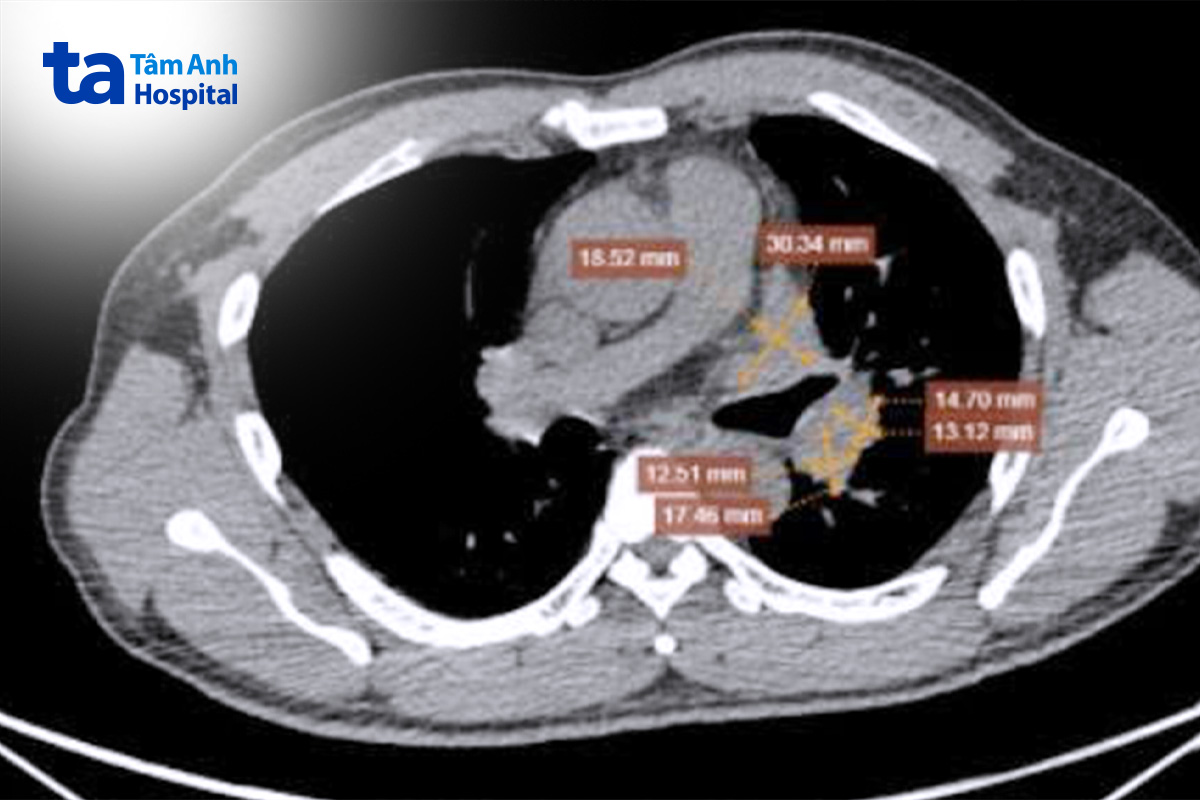

BS.CKII Nguyễn Thành Trung, Khoa Ung bướu, Bệnh viện Đa khoa Tâm Anh Hà Nội cho biết phim chụp CT và PET/CT của ông Dũng cho thấy khối u ác tính từ phổi trái kích thước khoảng 58x29mm, xâm lấn qua màng phổi trung thất lân cận tạo thành khối lớn tại rốn phổi trái kích thước 33x24mm, di căn xương cột sống. Bệnh ở giai đoạn IV, người bệnh không thể phẫu thuật mà cần chuyển sang phác đồ điều trị toàn thân.